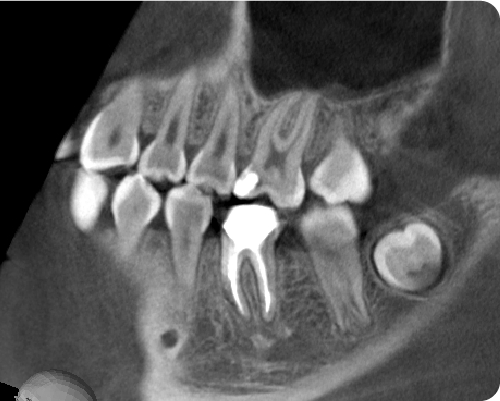

経験豊富なドクターによる丁寧な抜歯

Before

After

当院では、親知らずの抜歯を希望して来院される方に、安心・安全な医療を提供できるよう、万全な体制、アフターフォローを整えております。